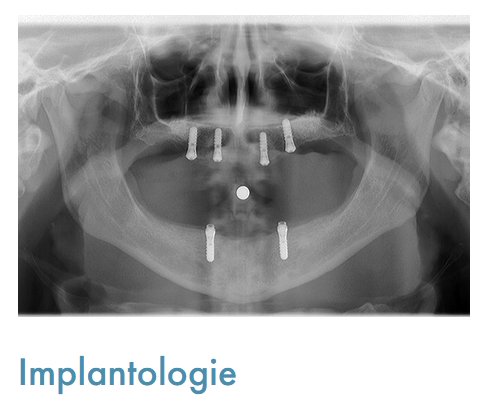

Notre cabinet comprend également un local dédié à la radiologie numérique, incluant une radiographie panoramique, permettant des diagnostics précis et rapides. Grâce à notre équipement de pointe, nous assurons une prise en charge optimale de chaque patient.

• Implantologie : Nous pratiquons la pose d'implants dentaires, offrant ainsi une solution durable et fiable pour le remplacement de dents manquantes.